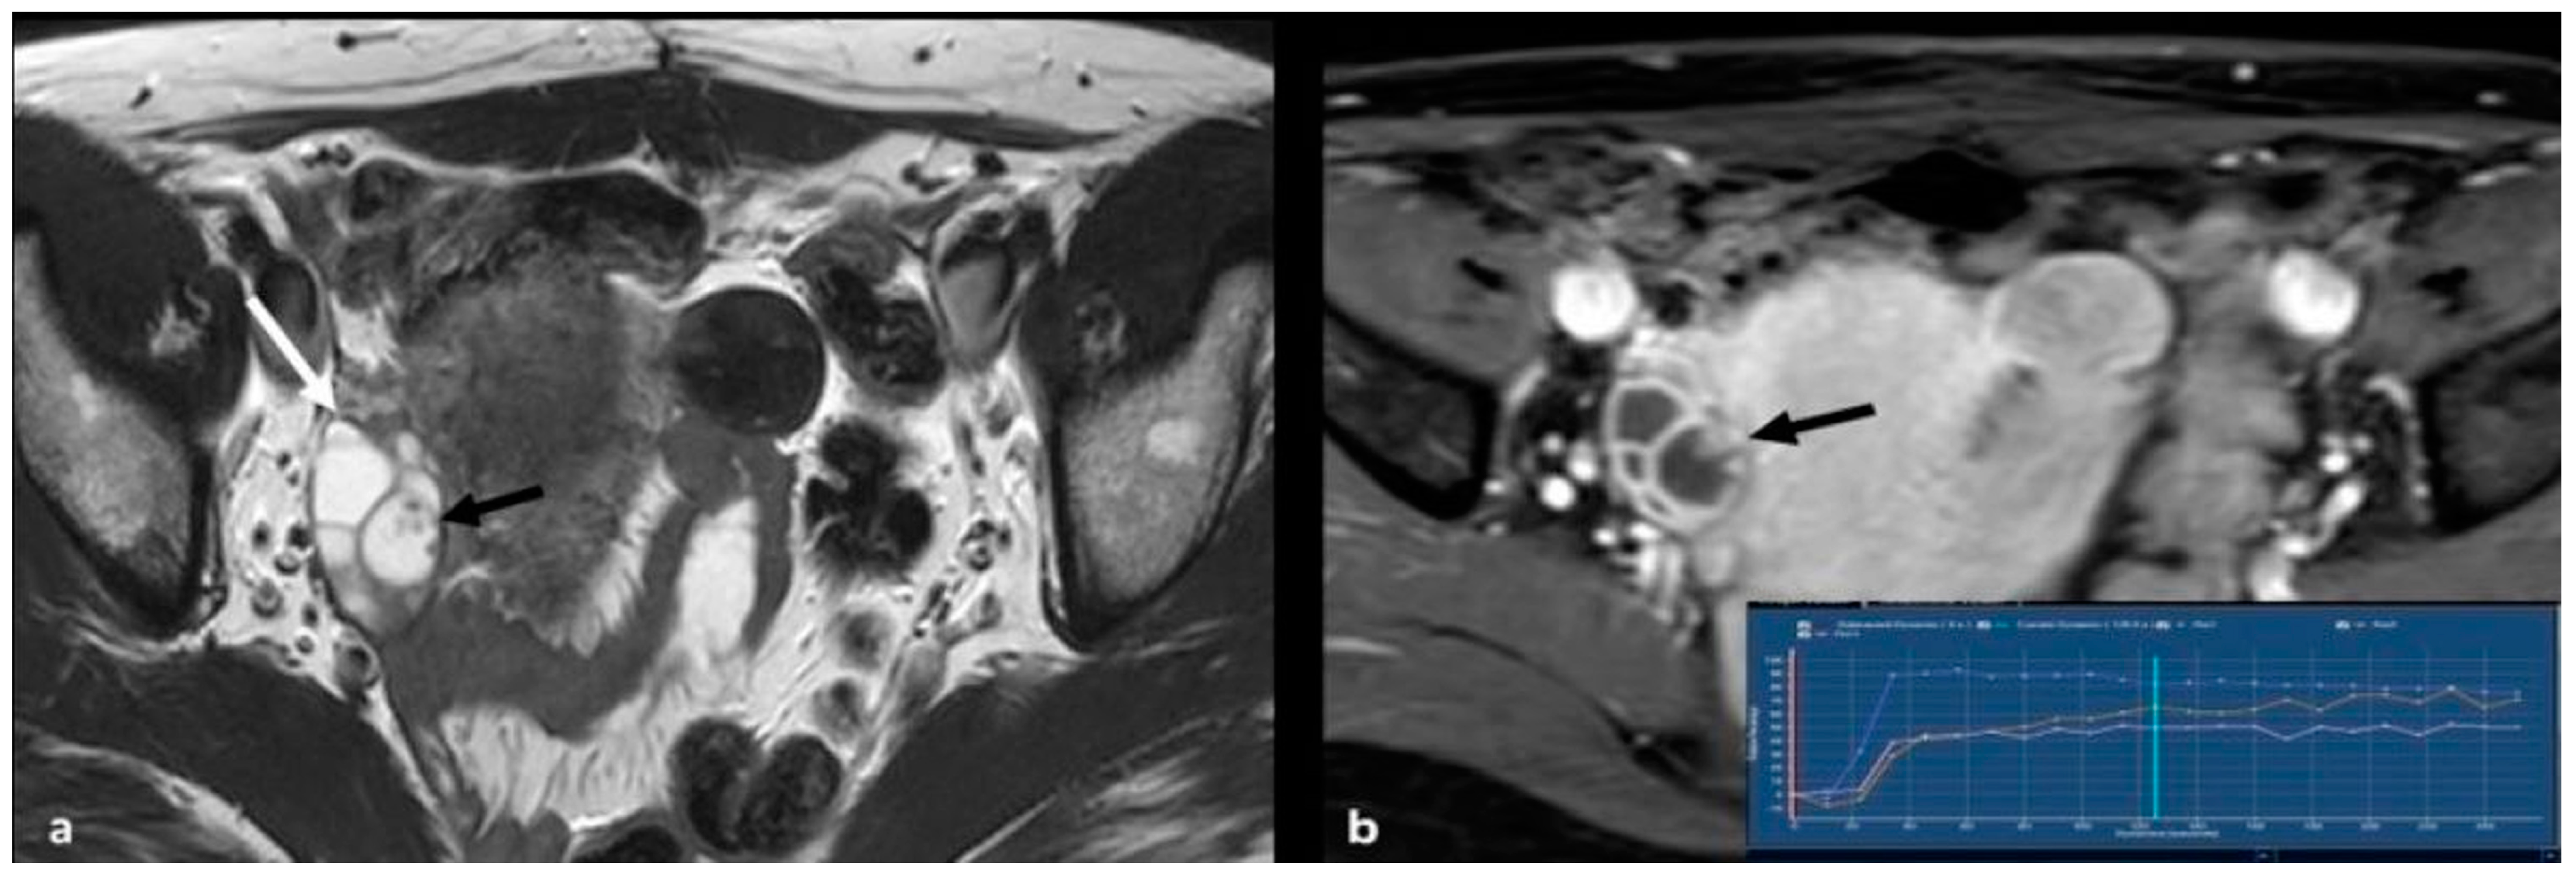

2.3.3. Granulosa Cell Tumor

2.3.4. Lymphoma

2.3.5. Metastases